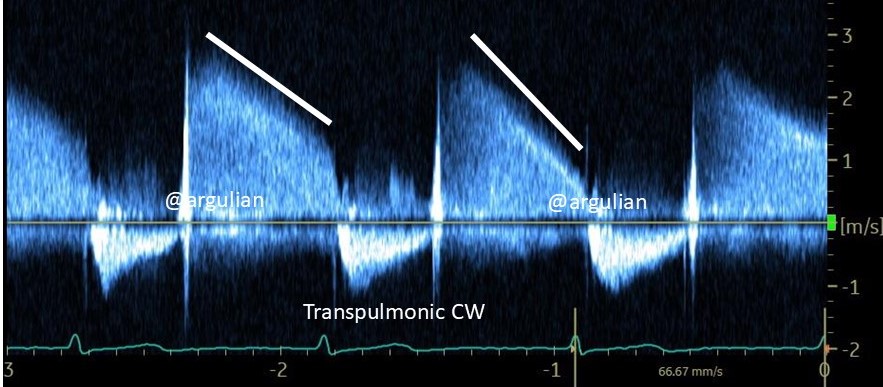

A complete guide on #tricuspid valve disease from clinical examination and #multimodality #imaging up to #surgery, complex #structural devices and the set up of dedicated valve centers, now published under @NatRevCardiol @NaturePortfolio - really grateful to @jgranadacrf for his mentorship and @hahn_rt @MartyBLeon @EZancanaroMD @kp_rommel @npfam1 @azeemlatib @FabienPraz @AugustinCoisne @modine_thomas @PhilippLurz @VDelgadoGarcia @masitges @j_hausleiter @nicolo_piazza